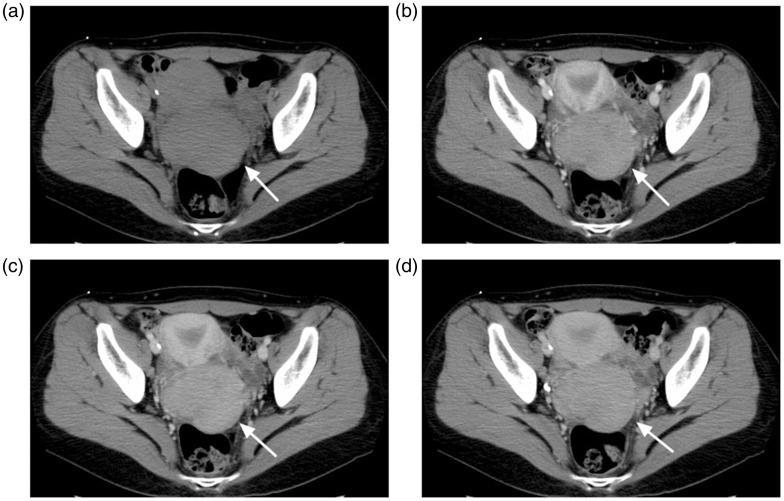

Imaging findings of solitary uterine granulocytic sarcoma.

A 29-year old woman with a history of vaginal bleeding was referred to our hospital. Transvaginal ultrasonography revealed a hypervascular cervical mass and malignancy was suspected. Computed tomography (CT), magnetic resonance imaging, and 18-F-fluorodeoxyglucose positron emission tomography/CT were performed. She was finally diagnosed with granulocytic sarcoma based on pathological examination.